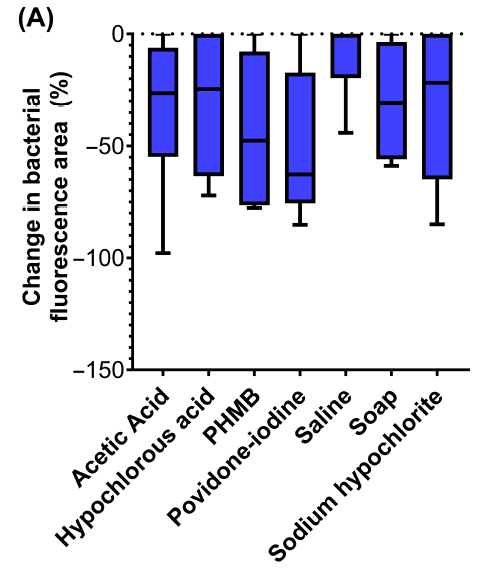

An objective comparative study of non-surgical cleansing techniques and cleanser types in bacterial burden management

Oropallo, A. et al. Int Wound J 2024